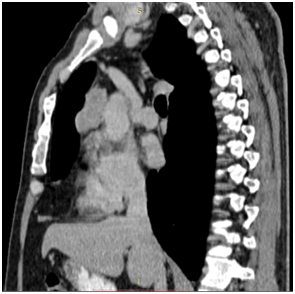

1stCase presentation

The 1st case we report is of a 22-year-old Caucasian male, who was admitted to our hospital with a 3-days history of progressive dyspnea on exertion, neck swelling, fatigue, persistent chest pain, pyrexia, and a cough that was occasionally productive of blood. The physical examination revealed a heart rate of 115 beats per minute (Sinus Rhythm), a respiratory rate of 25 breaths per minute and superficial vascular distention over the neck. Laboratory studies revealed elevated serum α-fetoprotein (AFP) (5380 IU/ml) and D-dimer (481ng/ml). A chest X-ray in the poster - anterior view, upon admission, depicted a suggestive right upper mediastinal mass (Bild 1). Radiography was followed by contrast-enhanced CT scan that revealed a large, homogeneous mediastinal mass crossing into the anterior mediastinum and compressing – encasing the superior vena cava. It also showed signs of thrombosis of the left brachiocephalic vein, and multiple filling defects at the left pulmonary artery indicating embolism. Subcarinal lymphadenopathy, as well as enlarged lymph nodes of the right hilum was present (Bild’s 2-5). On median sternotomy, a large non resectable tumor was observed involving the in nominate vein and the superior vena cava (Bild 6). Great care was taken to remove as much tumor mass as possible. To decompress the superior vena cava, we had to perform an extensive resection and reconstruction of the cephalad part of the superior vena cava using homolog pericardium.A histopathological examination of a section of the mass revealed a mixed NSGCT (embryonal yolk sac/endodermal sinus tumour), containing also elements of embryonal carcinoma (Figure 1-6).The patient was placed on cisplatin-based chemotherapy (BEP regimen: cisplatin 50mg/m2 on days 1-2, etoposide 165mg/m2 on days 1-3, bleomycin 30U on days 1, 8, and 15, every 3 weeks). Tumor markers were elevated for a-FP (214ng/mL) and normal for β-HCG. The patient completed 4 cycles of chemotherapy and the subsequent chest CT (Bild 7) revealed a partial remission of the mass (decrease>50% of the size). The a-FP was normal as well as the β-HCG. The remaining mass was inoperable so the patient was started on salvage chemotherapy with the TIP (paclitaxel, ifosfamide, ciplatin) regimen for 4 cycles. The post-chemo chest CT showed stable disease and the patient was referred to radiation oncologists for radiotherapy of the remaining tumor. Three months later af P was found elevated and the CTs revealed multiple brain metastases. Whole brain radiation was performed and the patient was placed on gemcitabine (d1 and d8 every 21 days). Two months later the neurologic status deteriorated with new brain metastases and the patient passed away (19 months after the diagnosis).

Bild 1 Yolk sac tumor. The initial chest radiograph demonstrating soft tissue fullness along the right hilum and mediastinum that obscures the hilar anatomy.